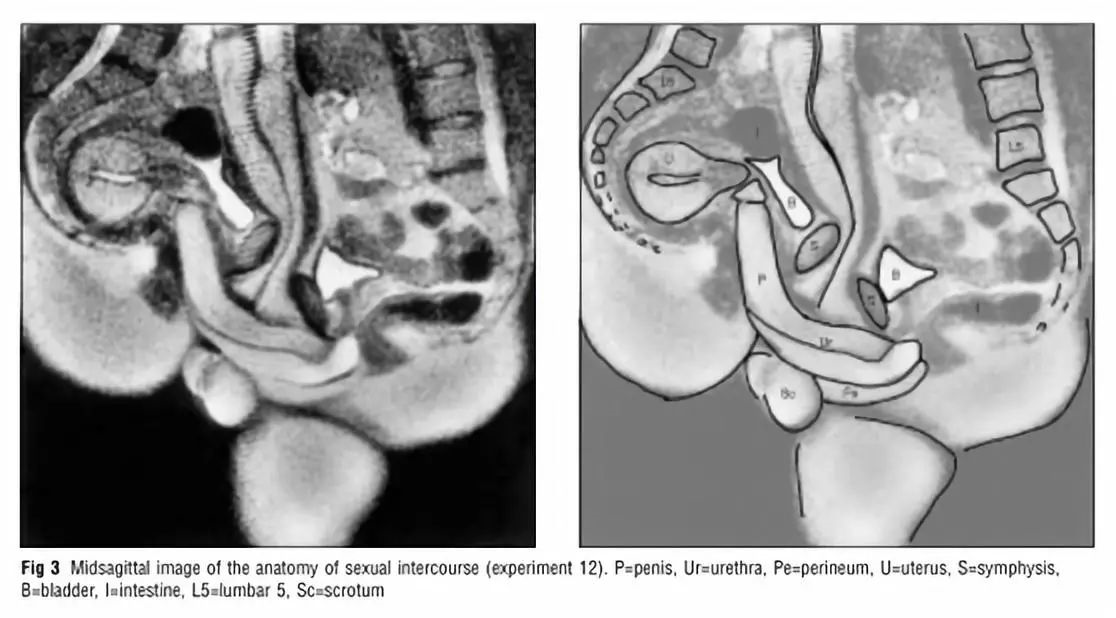

今年圣诞节,BMJ也迎来了其最火论文的20周年纪念,至于这篇论文为什么会火,想必大家看了论文标题就会立即服气了:利用核磁共振观测男女交配和女性性唤起时双方的生殖器状态。

当然,既然现在有了这篇神圣论文,那就说明研究者还是克服重重困难拿到了人类交配时生殖器的核磁共振图。结果显示,使用正常的传教士体位(男上女下)时,男性生殖器既不是完全笔直的也不是之前预测的S形状,而是呈现出回力镖的形状。而女性性唤起时,子宫也不会像之前报道的一样增大,而是保持不变。不过交配开始后,女性子宫会增大约2.4cm,同时膀胱也会增大。

科学、文明观图。